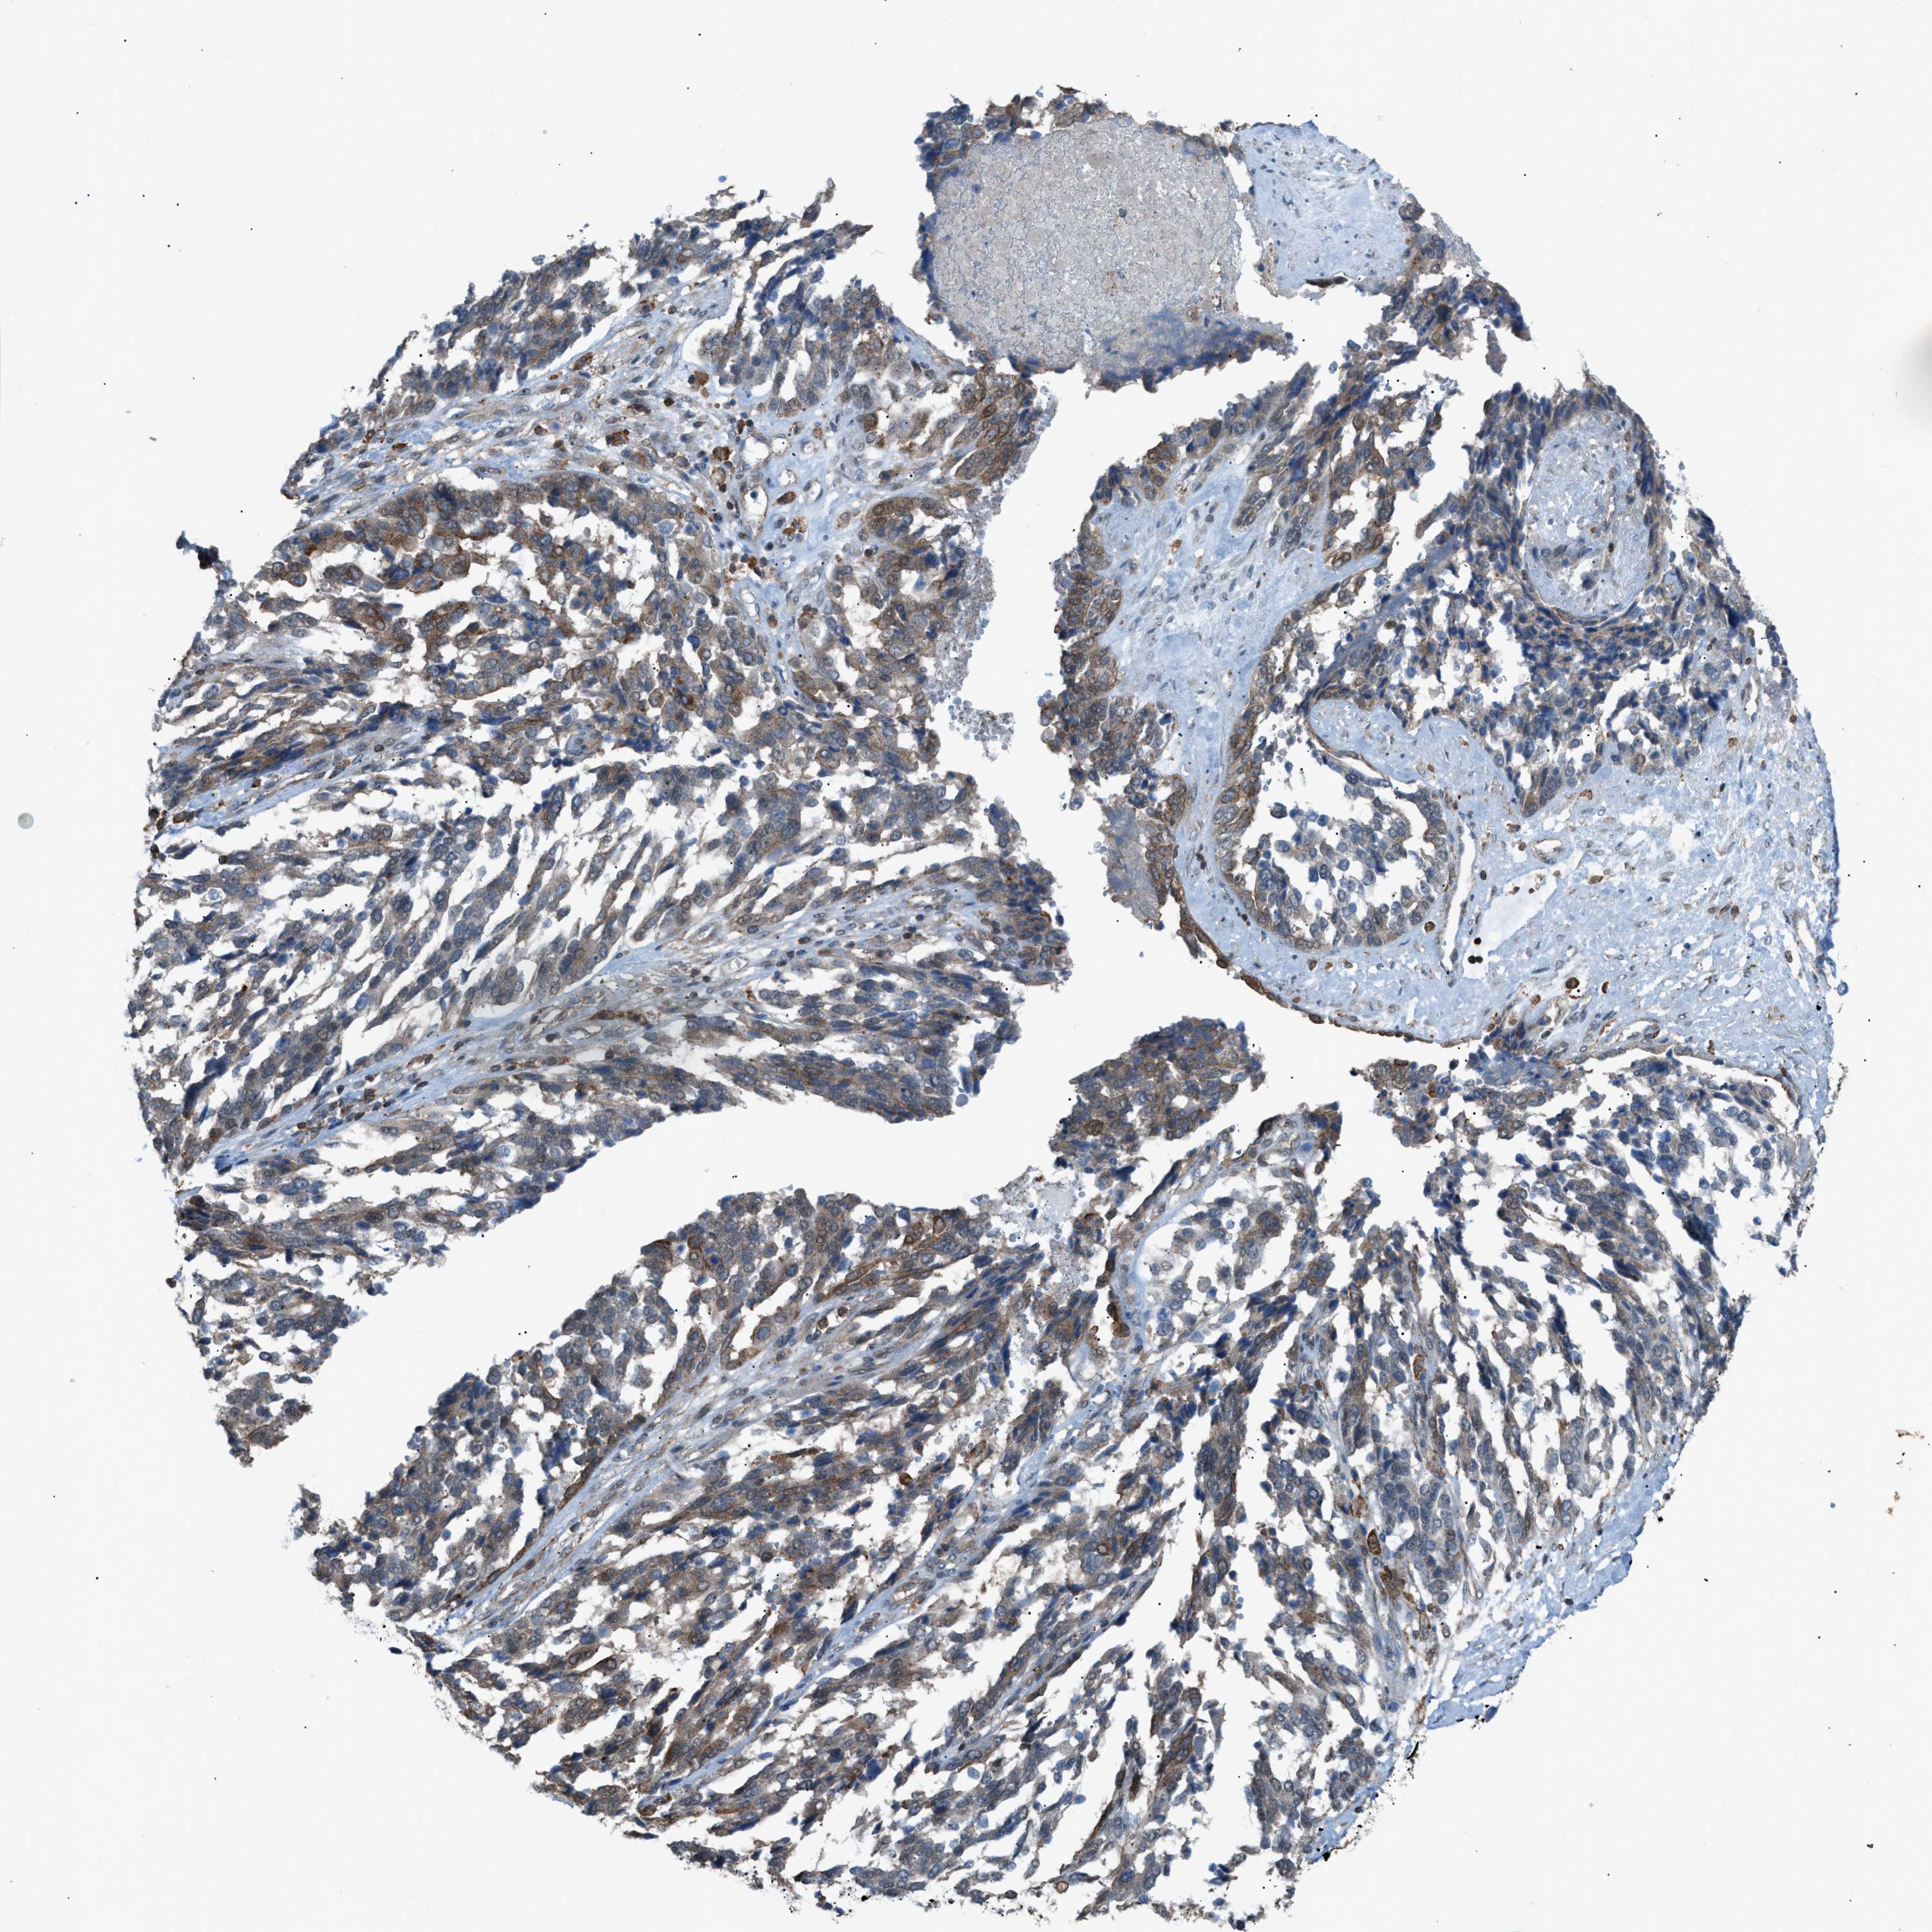

OVARIAN CANCER - Protein expressioni

A mouse-over function shows sample information and annotation data. Click on an image to view it in a full screen mode. Samples can be filtered based on level of antibody staining by selecting one or several of the following categories: high, medium, low and not detected. The assay and annotation is described here.

Note that samples used for immunohistochemistry by the Human Protein Atlas do not correspond to samples in the TCGA dataset.

Antibody stainingi

Antibody staining in the annotated cell types in the current human tissue is reported as not detected, low, medium, or high, based on conventional immunohistochemistry profiling in selected tissues. This score is based on the combination of the staining intensity and fraction of stained cells.

Each image is clickable and will lead to virtual microscopy that enables deeper exploration of all samples and also displays staining intensity scores, fraction scores and subcellular localization as well as patient and tissue information for each sample.

Antibody HPA015323

Antibody HPA015810

Carcinoma, endometroid

Cystadenocarcinoma, serous, NOS

Cystadenocarcinoma, mucinous, NOS

Carcinoma, NOS